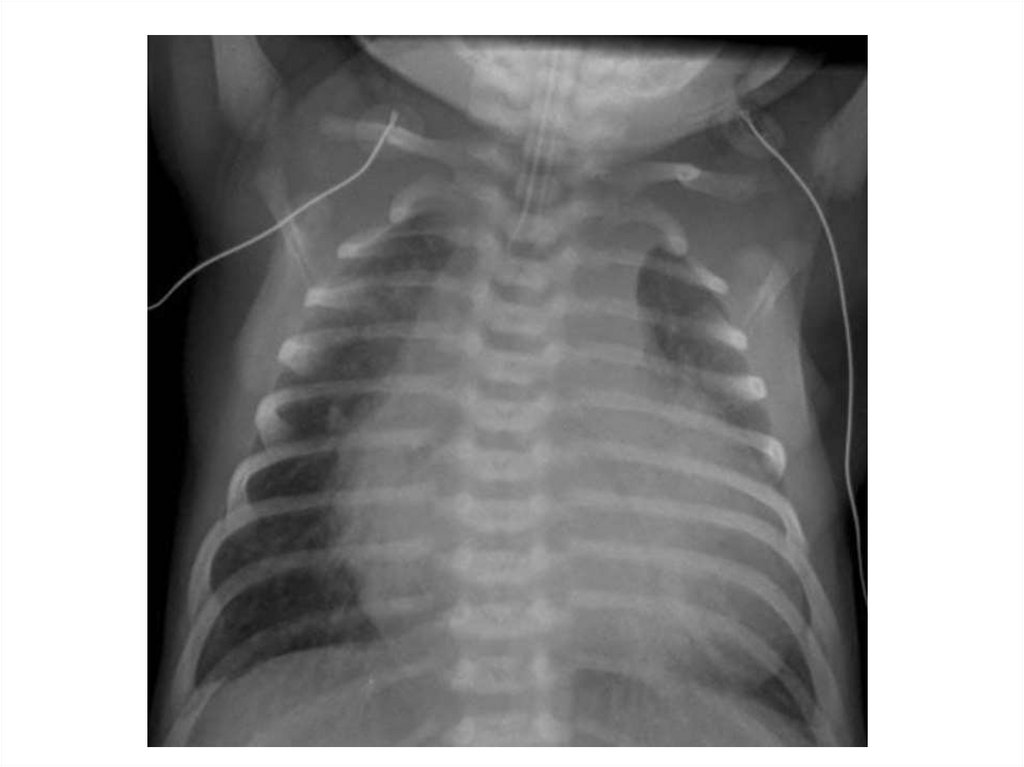

Назовите

• Вид исследования

• Область исследования

• Патологию